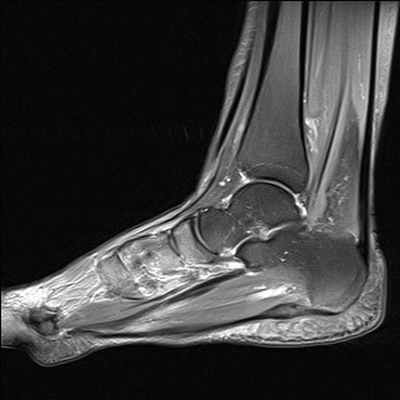

МРТ голеностопного сустава

Минимальные костные повреждения, обычно не выявляемые при рентгене, хорошо визуализируются при МРТ и КТ.

Для выявления изменений внесуставных стабилизаторов голеностопного сустава УЗИ и МРТ имеют примерно одинаковую диагностическую информативность. Оптимальным видом лучевого исследования для выявления изменений внутрисуставных структур голеностопного сустава является МРТ.

МРТ является наиболее универсальным методом визуализации повреждений всех структур голеностопного сустава. КТ позволяет детализировать (оценить степень и распространенность) выявленных при МРТ минимальных костных переломов. Повреждение связок по данным некоторых авторов в 16-21% случаев сопровождает спортивные травмы голеностопного сустава. При острой травме чаще всего повреждается передняя таранно-малоберцовая связка, реже - пучки дельтовидной связки.

Поскольку острые повреждения связок редко лечатся хирургически, магнитно-резонансная томография чаще всего назначается при наличии клинических признаков нестабильности сустава для решения вопроса о тактике ведения пациента и профпригодности.

МРТ критерии диагностики острых разрывов включают изменение интенсивности сигнала внутри и вокруг связок, прерывистость волокон, исчезновение жировых включений в структуре связки, признаки отека окружающих мягких тканей, контузию сочленяющихся костей.

По данным P.W. Bearcroft и соавт. чувствительность МРТ в выявлении острых повреждений связок голеностопного сустава составляет 94-96%, для хронических разрывов – 82-90%. МРТ обладает наибольшей чувствительностью (96-97%) и специфичностью (98%) в выявлении стрессовых переломов на ранней стадии.